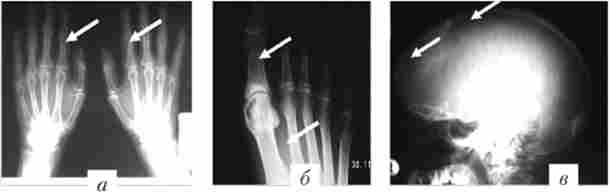

рентгенологічні дослідження черепа виявляють дифузний остеопороз, що вражає близько 2/3 кісток (рис. 7.2). Проксимальні відділи довгих кісток остеопоротичних, з кістами. Кістки кистей рук з суперіостальної резорбцией проксимальних і середніх фаланг, іноді з кальцификацией судин пальців.

Виражений остеопороз з утворенням кіст (відзначені стрілками) у хворої первинним гінернаратіреозом

Мал. 7.2. Виражений остеопороз з утворенням кіст (відзначені стрілками) у хворий первинним гінернаратіреозом:

а - в кістках кистей; 6 - в кістках стоп; в - в зведенні черепа